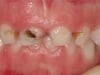

Early Childhood Caries